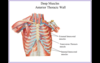

ANATOMY: RESPIRATORY SYSTEM Flashcards

A

10

Q

Identify